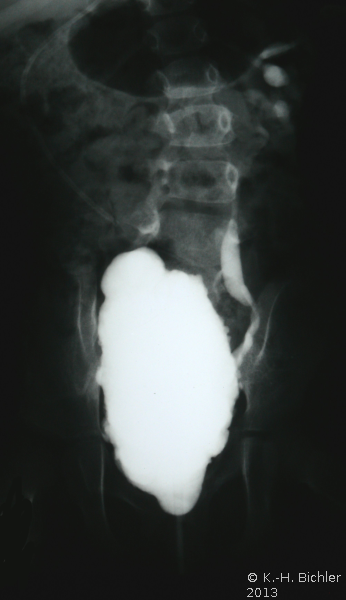

Ein VUR war nicht mehr nachweisbar (Abbildung 17ab).